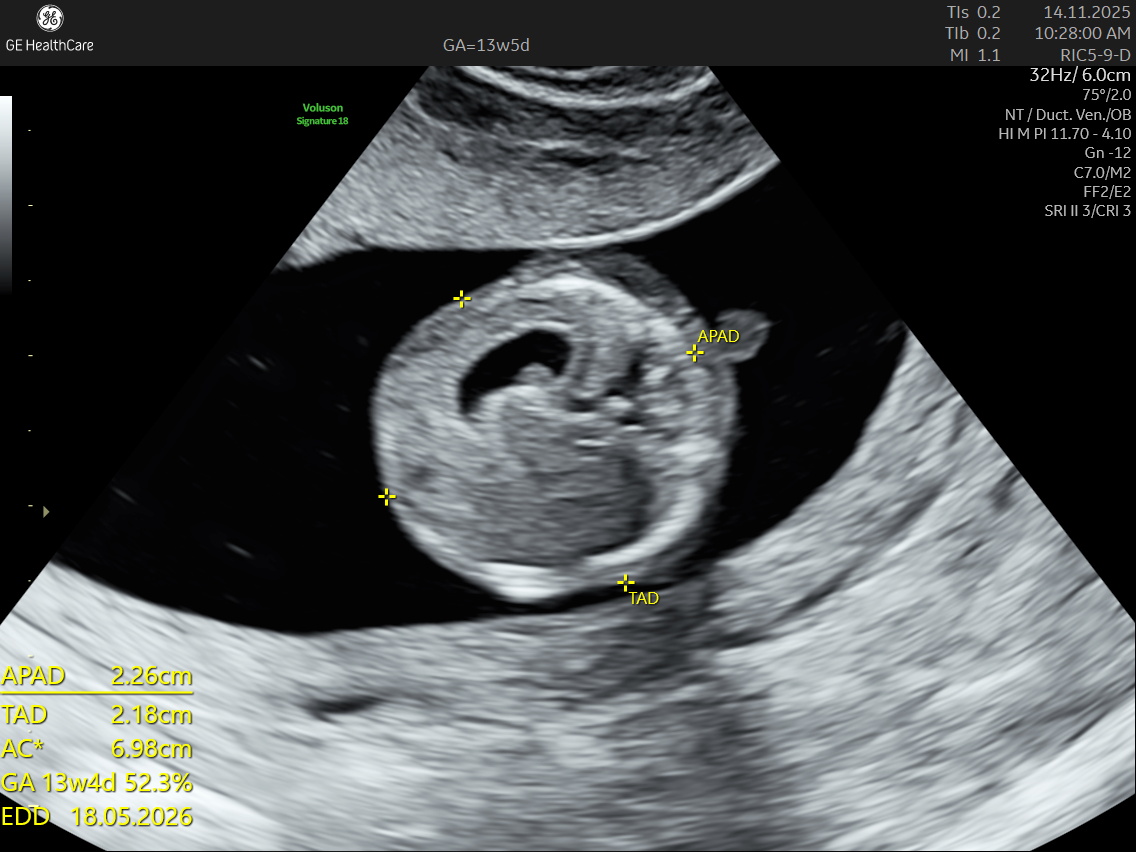

The NT scan is a non-invasive ultrasound examination conducted in the first trimester (12–13 weeks). It measures the nuchal translucency (the fluid at the back of the fetus’s neck) and combines it with the maternal blood test for a detailed risk profile. NT Scan is an important early screening test for Down syndrome (Trisomy 21), Edwards syndrome (Trisomy 18), and Patau syndrome (Trisomy 13).

Although the NT scan is mainly a screening tool and not diagnostic on its own, it can identify about 50% of major fetal abnormalities when combined with other assessments like blood tests and detailed ultrasound. The scan also helps to screen some basic anatomical structures during the first trimester, especially the fetal heart anatomy, brain, face, spine, stomach, abdominal wall, kidneys, bladder, and extremities to varying degrees depending on gestational age and maternal factors.